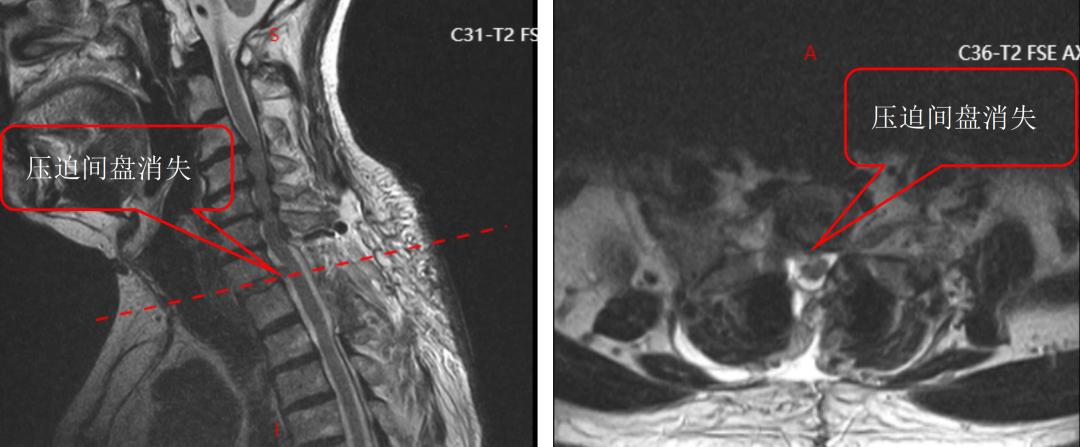

通过与骨科手术机器人配合,整个手术过程顺利完成,螺钉置入位置精准无误,患者术中出血量大幅减少,手术时间也得到有效优化,手术效率和安全性实现双重提升。

术后复查结果也令人振奋,患者螺钉位置良好,椎管减压彻底,原本麻木、无力的双下肢症状明显改善,行走能力逐步恢复。看着老先生摆脱病痛困扰,脸上重新露出笑容,医护人员也倍感欣慰。